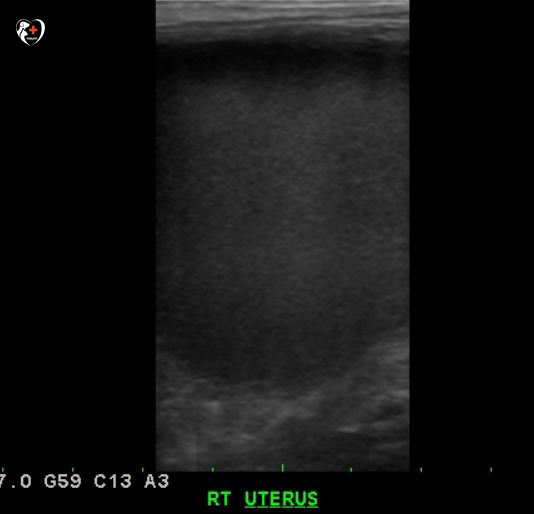

복부 초음파 검사를 실시하여 비뇨기계, 생식기계를 샅샅이 조사해 본 결과, 오른쪽 확장 자궁이 보였습니다.

오른쪽 사진을 보면 자궁이 크게 펼쳐져 있고 검은 부분이 잘려져 있군요?자궁축농증으로 인해 커진 것으로 확인되었습니다.